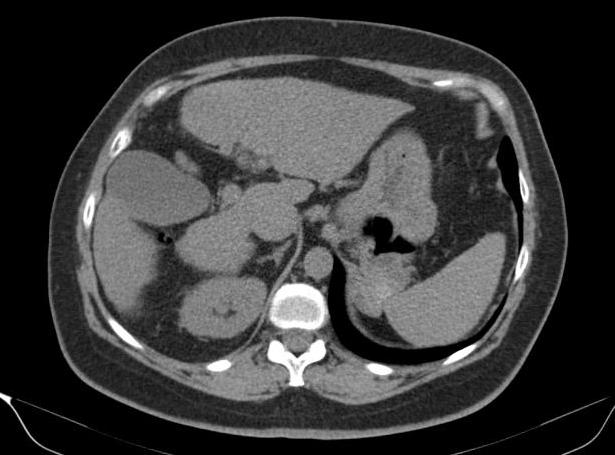

Túi thừa dạ dày

» Thông tin: Nữ giới – 54 tuổi.

» Lâm sàng: Kiểm tra sức khỏe.